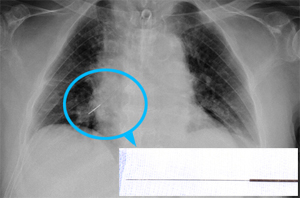

결국 보도 내용을 토대로 한의협은 긴급 회견 이후 서울중앙장방검찰청에 '노 전 대통령의 흉부 우측 주 기관지에서 발견된 침을 시술한 자'를 수사해달라며 진정서를 제출했다. 동시에 보건복지부에도 직권조사를 의뢰했다.

뜸사랑은 "통상의 침치료로서 침이 기관지로 들어간다는 건 상식적으로 이해 할 수 없는 일"이라며 "지금까지 100만명 이상의 환자에게 침뜸봉사를 하면서 아무런 의료분쟁에 휘말리지 않았던 뜸사랑을 음해하기 위한 불순한 기도"라고 지적했다.